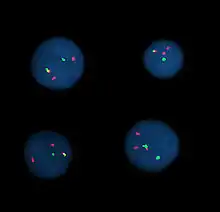

Cytogenetics is essentially a branch of genetics, but is also a part of cell biology/cytology (a subdivision of human anatomy), that is concerned with how the chromosomes relate to cell behaviour, particularly to their behaviour during mitosis and meiosis.[1] Techniques used include karyotyping, analysis of G-banded chromosomes, other cytogenetic banding techniques, as well as molecular cytogenetics such as fluorescent in situ hybridization (FISH) and comparative genomic hybridization (CGH).

Fluorescent in situ hybridization

Fluorescent in situ hybridization (FISH) refers to using fluorescently labeled probe to hybridize to cytogenetic cell preparations.

The slide is aged using a salt solution usually consisting of 2X SSC (salt, sodium citrate). The slides are then dehydrated in ethanol, and the probe mixture is added. The sample DNA and the probe DNA are then co-denatured using a heated plate and allowed to re-anneal for at least 4 hours. The slides are then washed to remove the excess unbound probe, and counterstained with 4',6-Diamidino-2-phenylindole (DAPI) or propidium iodide.

Analysis

Analysis of FISH specimens is done by fluorescence microscopy by a clinical laboratory specialist in cytogenetics. For oncology, generally, a large number of interphase cells are scored in order to rule out low-level residual disease, generally between 200 and 1,000 cells are counted and scored. For congenital problems usually 20 metaphase cells are scored.